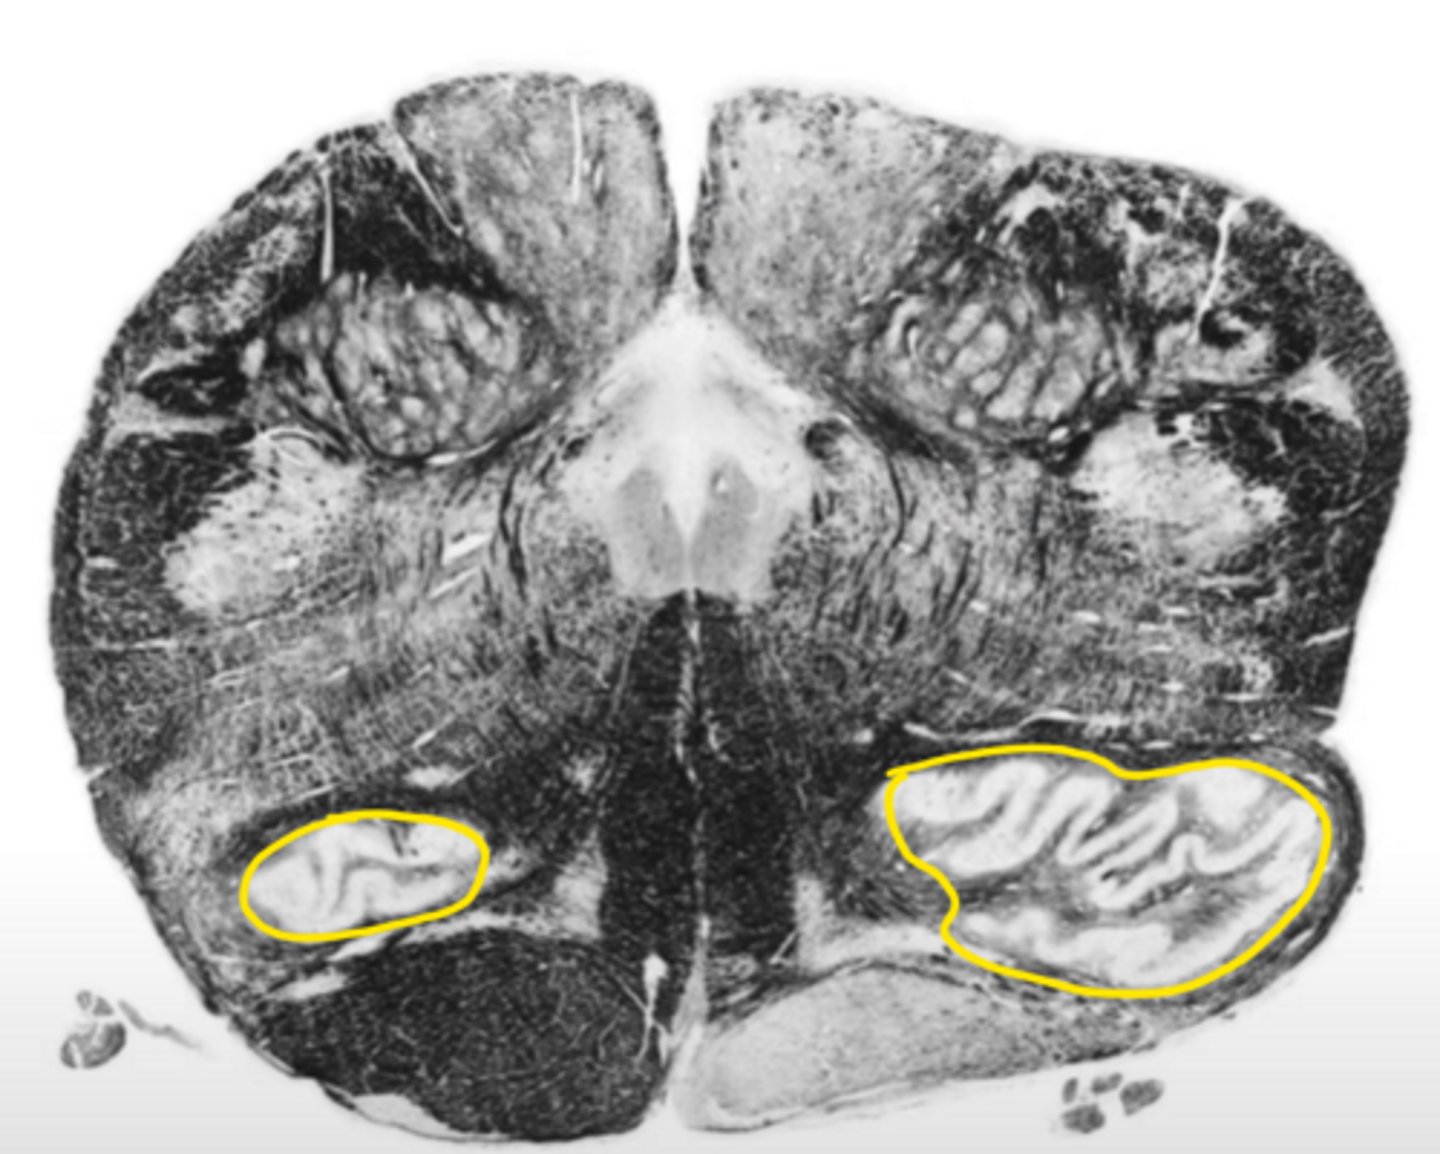

olive

ID the structure

principle olivary nucleus